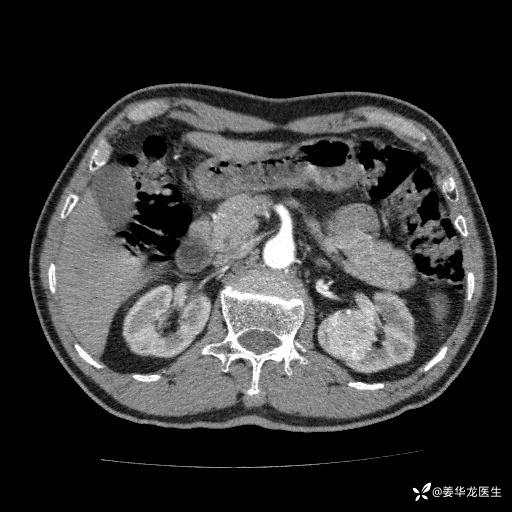

左肾中心型肾门部肿瘤39mm×34mm×36mm,右肾GFR25ml/min,部分切还是全切?

患者75岁老年男性,体重50kg,无高血压、肾病、糖尿病等基础病,检查发现左肾中心型肾门部肿瘤,右肾GFR只有25ml,无肉眼血尿,无镜下血尿。入院验血常规检查均正常,包括肾功能,肌酐102.7umol/L.

二、左肾肿瘤与左肾集合系、左肾动静脉关系密切,左肾部分切除术可行吗?成功率有多大?成功部分切后,肾功能还有多少?